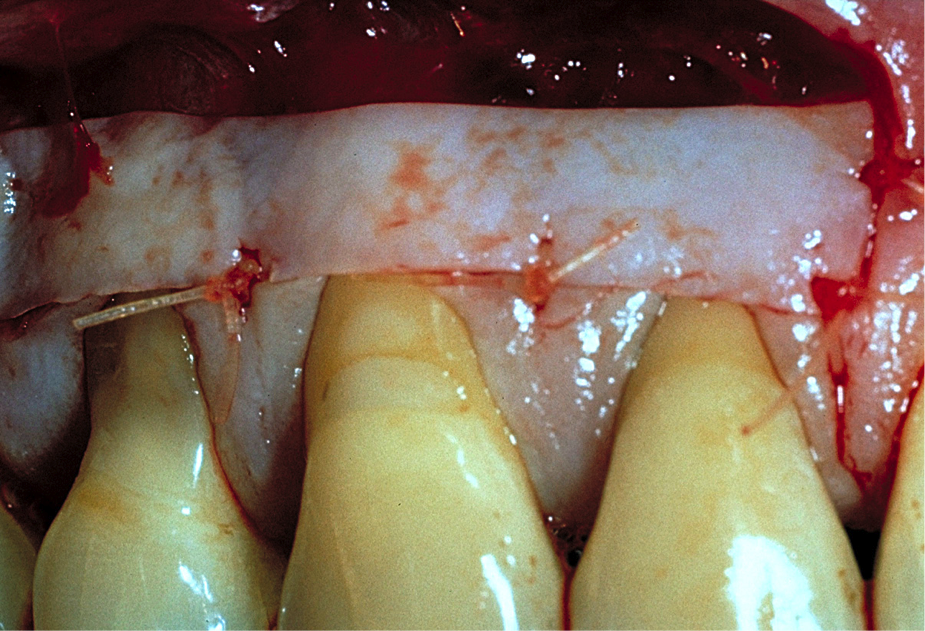

The graft is undermined by making an incision into the connective tissue layer using a #15C scalpel, leaving the epithelial layer intact (Figure 2). The tissue can then be lifted away and freed from the palate (Figure 3), after which it can be trimmed as necessary and ultimately transplanted back to the patient. The palate is then covered with a positive-pressure stent worn by the patient continuously for 1 week postoperatively, except when cleaning the stent after eating. During the second week postoperatively, the patient wears the stent only when eating. The palate is expected to be fully healed after the second week and then no longer requires protection. Surgical dressing is placed on the graft recipient site to reduce postoperative discomfort and facilitate proper healing of the graft site.

The graft was placed to the height of the original free gingival margin (FGM) (Figure 5), and no attempt was made to cover what had been the exposed root areas—the only areas covered were where biologic attachment had been previously. Interproximal sutures were used to hold the FGG in place, and a surgical dressing was applied. Figure 6 shows successful 13-year results.

Note that when FGGs fit passively onto the recipient site with complete contact on the underlining recipient bed, apical sutures are not required. However, when grafts tend to lift off the recipient site, from which the grafts obtain their blood supply, apical sutures are necessary to maintain intimate contact and fit.11,14,17